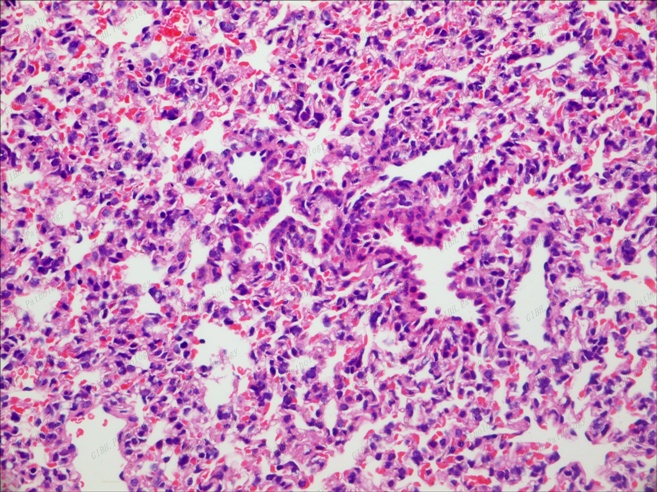

肺泡40